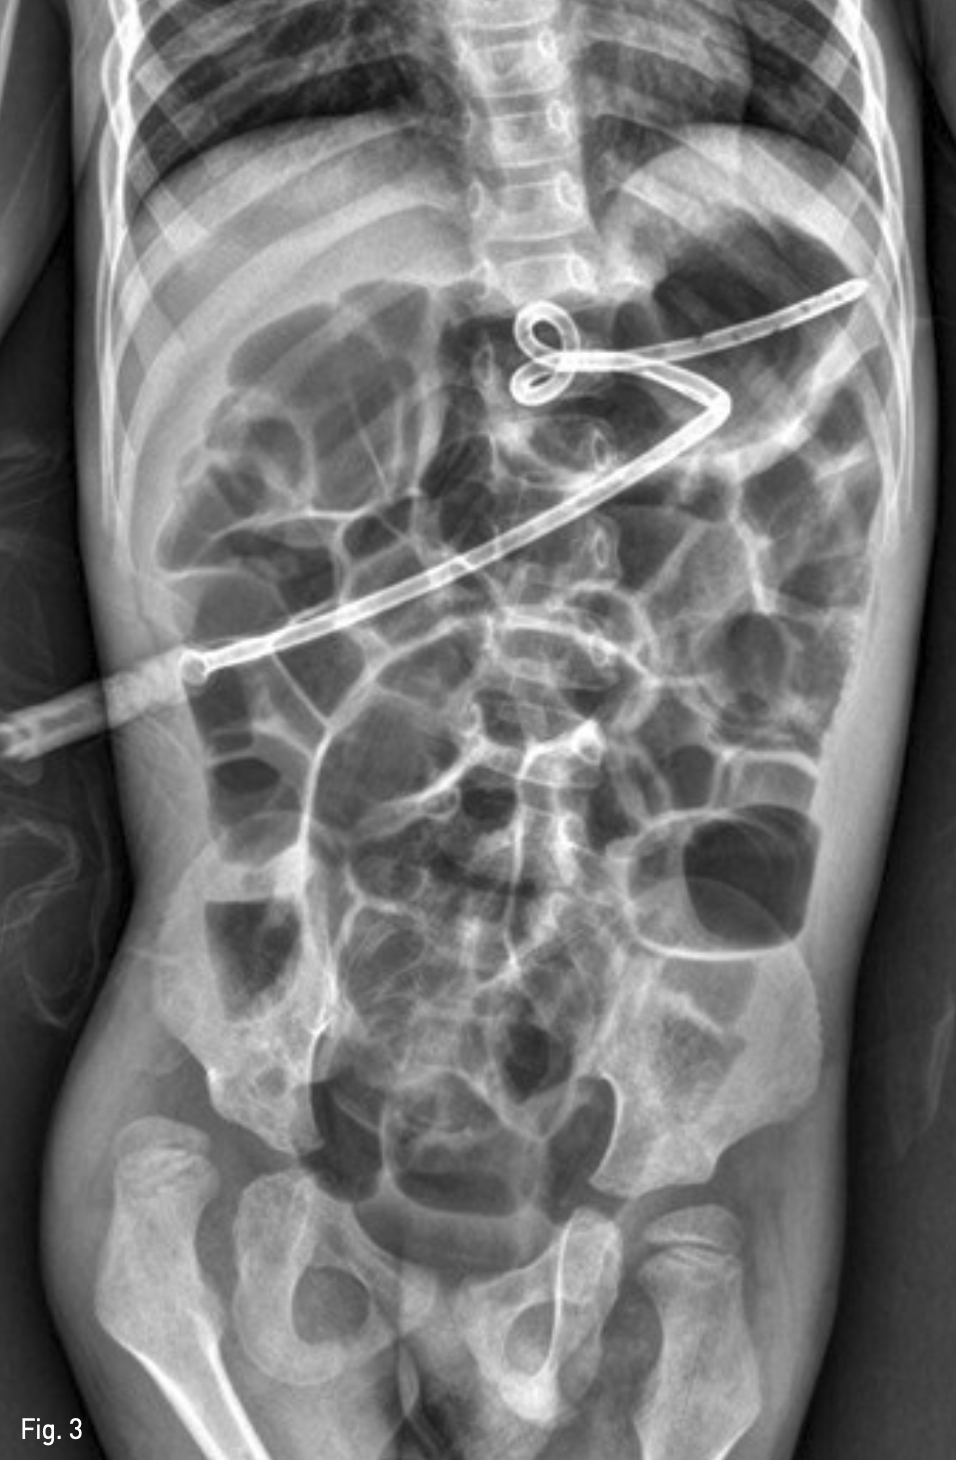

Fig. 1A

An upright abdomen roentgenogram, obtained 1 day after percutaneous radiologic gastrostomy shows large amount of pneumoperitoneum.

시술 다음 날 추적 관찰 단순 복부 X-ray 촬영에서 기복증이 발생하였고(Fig. 1A), 복부 CT에서는 위 전벽이 전복벽에 완전히 밀착되지 않았음을 확인하였다 (Fig. 1B). 기복증의 양이 작아 추적 관찰을 하였으나, 갈수록 양이 많아지고, 아울러 환아의 전신 상태가 나빠지기 시작하였음.